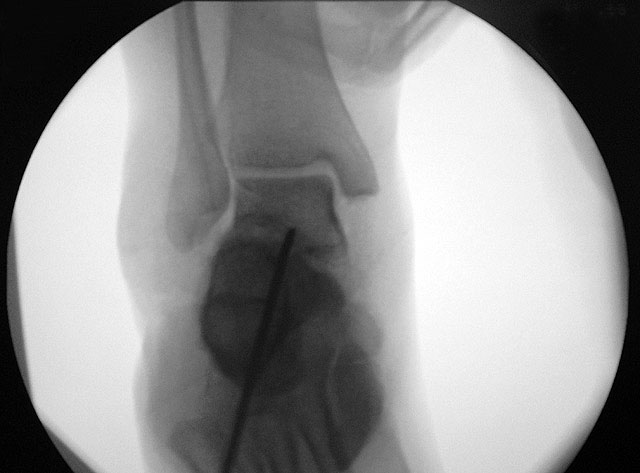

Je nach Operationsziel wird die Arthrodese des Subtalargelenks in verschiedenen Modifikationen durchgeführt. Ist der Rückfuß orthograd ausgerichtet, so erfolgt sie als in situ Fusion, d.h. ohne Korrektur Änderung der Rückfussachse. Liegt eine Rückfuß-Fehlstellung vor, kann diese durch ein additives oder substraktives knöcherndes Vorgehen korrigiert werden 12. Die Fixation der Arthrodese erfolgt üblicherweise mit (kanülierten) Schrauben die über den Tuber calcanei eingebracht werden 3. Eine zweite Schraube zur Sicherung der Rotationsstabilität wird optional über den Processus anterior calcanei im Talushals verankert 4. Der am häufigste verwendete Zugang zum unteren Sprunggelenk verläuft lateral subfibular, alternative Zugänge sind medial oder posterior möglich 56. Ist keine relevante Korrektur notwendig kann der Eingriff auch arthroskopisch durchgeführt werden 78.

Schraubenfehllage: Bei der intra-operative Röntgen-Kontrolle muss der Fuß exakt seitlich und das obere Sprunggelenk ap eingestellt werden, um die korrekte Lage der Schrauben beurteilen zu können.